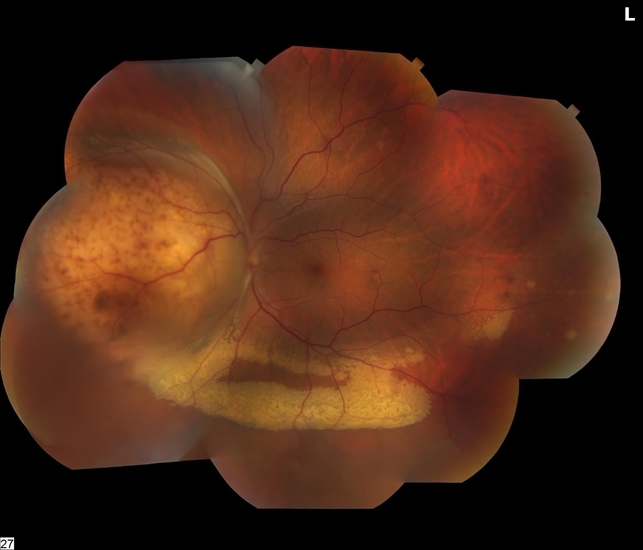

penile cancer photos download

Posts: penile cancer photos download